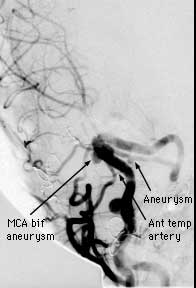

Findings: RCC angio shows the ICA follows an aberrent course, dipping inferiorly then laterally with no right A1 segment. A lobulated aneurysm involves the right MCA bifurcation. A second smaller aneurysm is present at the origin of the anterior temporal branch off the distal M1 segment. The normal left CC angiogram is shown for comparison.